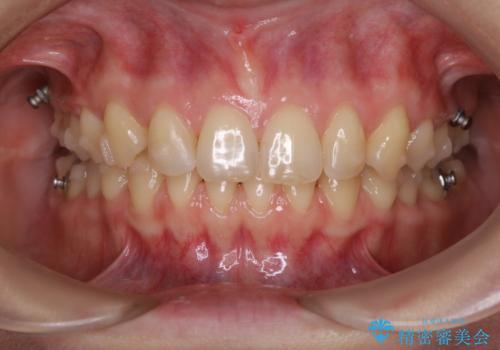

マウスピースをしたままコーヒーを飲むと着色がすごい

インビザライン中とインビザライン後のbefore、afterのクリーニング